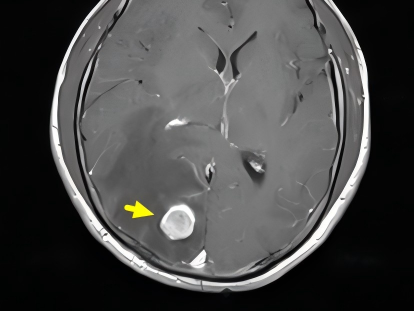

近日,我院神经外科成功完成一例神经导航辅助下的脑深部病变活检手术,为一名疑难病患者明确了诊断方向。 疑难病例 多系统病变待确诊 该患者为40岁男性,因长期咳嗽、头痛并发现双肺及颅内多发病变入院。初步检查倾向于感染性病变,但寄生虫、结核及肿瘤均需鉴别。虽经多项检查(包括发现蠊缨滴虫),抗感染治疗却效果不佳,且陆续发现全身多处淋巴结、肝脏及腰椎病变。由于肺部病变位置难以安全取材,经多学科讨论,决定对相对更适宜、风险更可控的脑部病灶进行活检。 神经导航 精准微创取病理 神经外科团队在神经导航系统的精准引导下,通过微小切口(皮肤8mm,颅骨钻孔5mm),成功获取了患者右侧枕叶一处直径仅1.5cm病变的组织样本,同期进行了颈部淋巴结活检。术后病理结果最终揭示了真相:肺低分化腺癌脑转移及淋巴结转移。 本例手术充分展现了神经导航技术在脑病变活检中的关键价值。其优势在于: 精确定位目标,优化手术路径。 实时可视化引导手术器械操作,避免传统穿刺的局限性。 显著提高获取病变组织的准确性。 有效提升手术安全性,降低并发症风险。 神经导航已成为现代神经外科提升手术精准化、微创化水平的重要支撑。随着其与术中影像、机器人等技术的不断融合,其应用潜力将进一步拓展。我院神经外科在精准定位手术领域积累了丰富经验。自2014年引进国产脑立体定向仪并成功自主开展首例手术以来,团队已累计完成包括脑深部病变活检在内的各类立体定向手术400余例。随着无框架神经导航技术的应用,其优势更加凸显。科室将持续提升先进设备的应用能力,为患者提供更全面、优质的诊疗服务。 神经外科专家简介 廖洪民 神经外科党支部书记、主任,主任医师 临床擅长:从事神经外科临床工作30年,对颅脑损伤、脑肿瘤、脑血管病等具有丰富诊疗经验,擅长救治重症颅脑创伤、脑出血微创治疗、脑肿瘤显微手术治疗、脑立体定向手术等。 中国医师协会神经外科分会专科认证医师、贵州省医学会神经外科分会青年委员、遵义市医学会神经外科分会常务委员、遵义市中西医结合学会脑心同治专业委员会常务委员、中国生命关怀协会脑卒中救治及康复照护专业委员会委员、贵州省脑损伤评价质控中心专家库成员、遵义市脑损伤评价医疗质量控制中心专家。 朱家伟 神经外科副主任医师 临床擅长:从事神经外科工作26年,擅长颅脑损伤救治及脑出血微创手术。 遵义市医学会神经外科分会委员、遵义市中西医结合学会脑心同治专业委员会常务委员。 黄建军 神经外科副主任医师 临床擅长:从事神经外科工作20年,对神经外科常见病、急危重症有丰富诊疗经验,熟练掌握神经外科微创手术。 神经外科科室简介 基本情况 贵州航天医院神经外科于2008年独立建科,是首批国家卫健委能力建设和继续教育神经外科建设中心,贵州省神经外科介入联盟单位。现有专业技术人员17人,其中高级职称4人,中级5人,初级7人。 科室配备STORZ神经内镜系统、德国莱卡手术显微镜,国产西山开颅动力系统、蛇牌双极电凝、Mayfield头架等颅脑手术设备,以及无创和有创颅内压监护仪、正中神经刺激仪、脑循环康复治疗仪、排痰机、下肢康复训练器、气垫床、多参数监护仪等现代化医疗设备,为病区各种急、危、重患者的观察、监护和治疗保驾护航。 专科特色 (一)脑出血微创手术治疗 应用范围:各种病因导致的自发性脑出血(高血压脑出血、脑淀粉样血管病相关脑出血、抗凝药物相关脑出血等)。 技术优势:微创、精准、恢复快。 (二)颅脑病变显微切除术 应用范围:颅内各种占位性病变(脑囊肿、脑肿瘤等)。 技术优势:精确度高、创伤小、恢复快。 (三)颅脑创伤综合救治 应用范围:各种类型的颅脑损伤、创伤性颅内血肿及颅脑创伤并发症、后遗症等。 技术优势:快速精准诊断、个体化手术与监护、早期康复干预,伤者病死率低、并发症少。